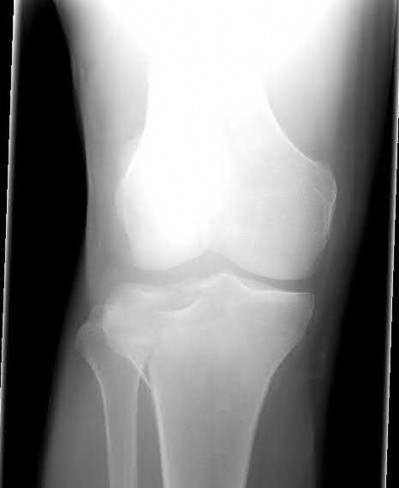

The safe zone for tibial nail placement as seen on radiographs is just medial to the lateral tibial spine on the anteroposterior radiograph and immediately adjacent and anterior to the articular surface as visualized on the lateral radiograph.

Tornetta et al specifically located the safe zone for nail entry in a study using fresh frozen cadaver knees. The authors found that the safe zone for nail placement is located 9.1+/-5 millimeters lateral to the midline of the plateau and three millimeters lateral to the center of the tibial tubercle. The width of the safe zone averaged 22.9 millimeters and was as narrow as 12.6 millimeters.

The starting point of the of the nail can be best viewed on the lateral knee radiograph, an example of which is shown in Illustration A. Illustration B shows the "sweet spot" for nail insertion as defined by Tornetta.